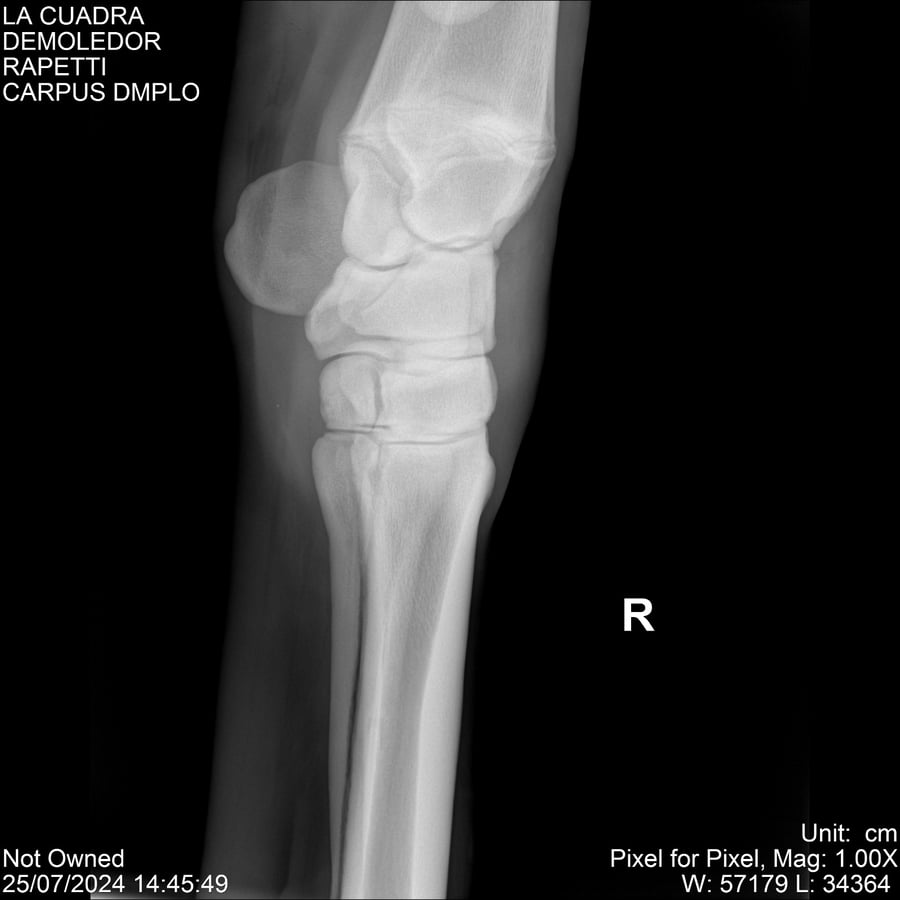

LOTE 14, DEMOLEDOR 🔥 🔥 🔥 Lote Anterior Volver al remate Lote Siguiente Ficha Contacto Montevideo - Ficha del Lote Identificador: #284454 Categoría: Yeguarizos Montevideo - 89 Visualizaciones ClicData Contacto Empresa: Abelenda N. R., Walter Hugo Nombre*: Teléfono* : E-mail* : Mensaje Enviar Registrese gratis Este contenido Exclusivo está disponible sólo para usuarios registrados Ingresar